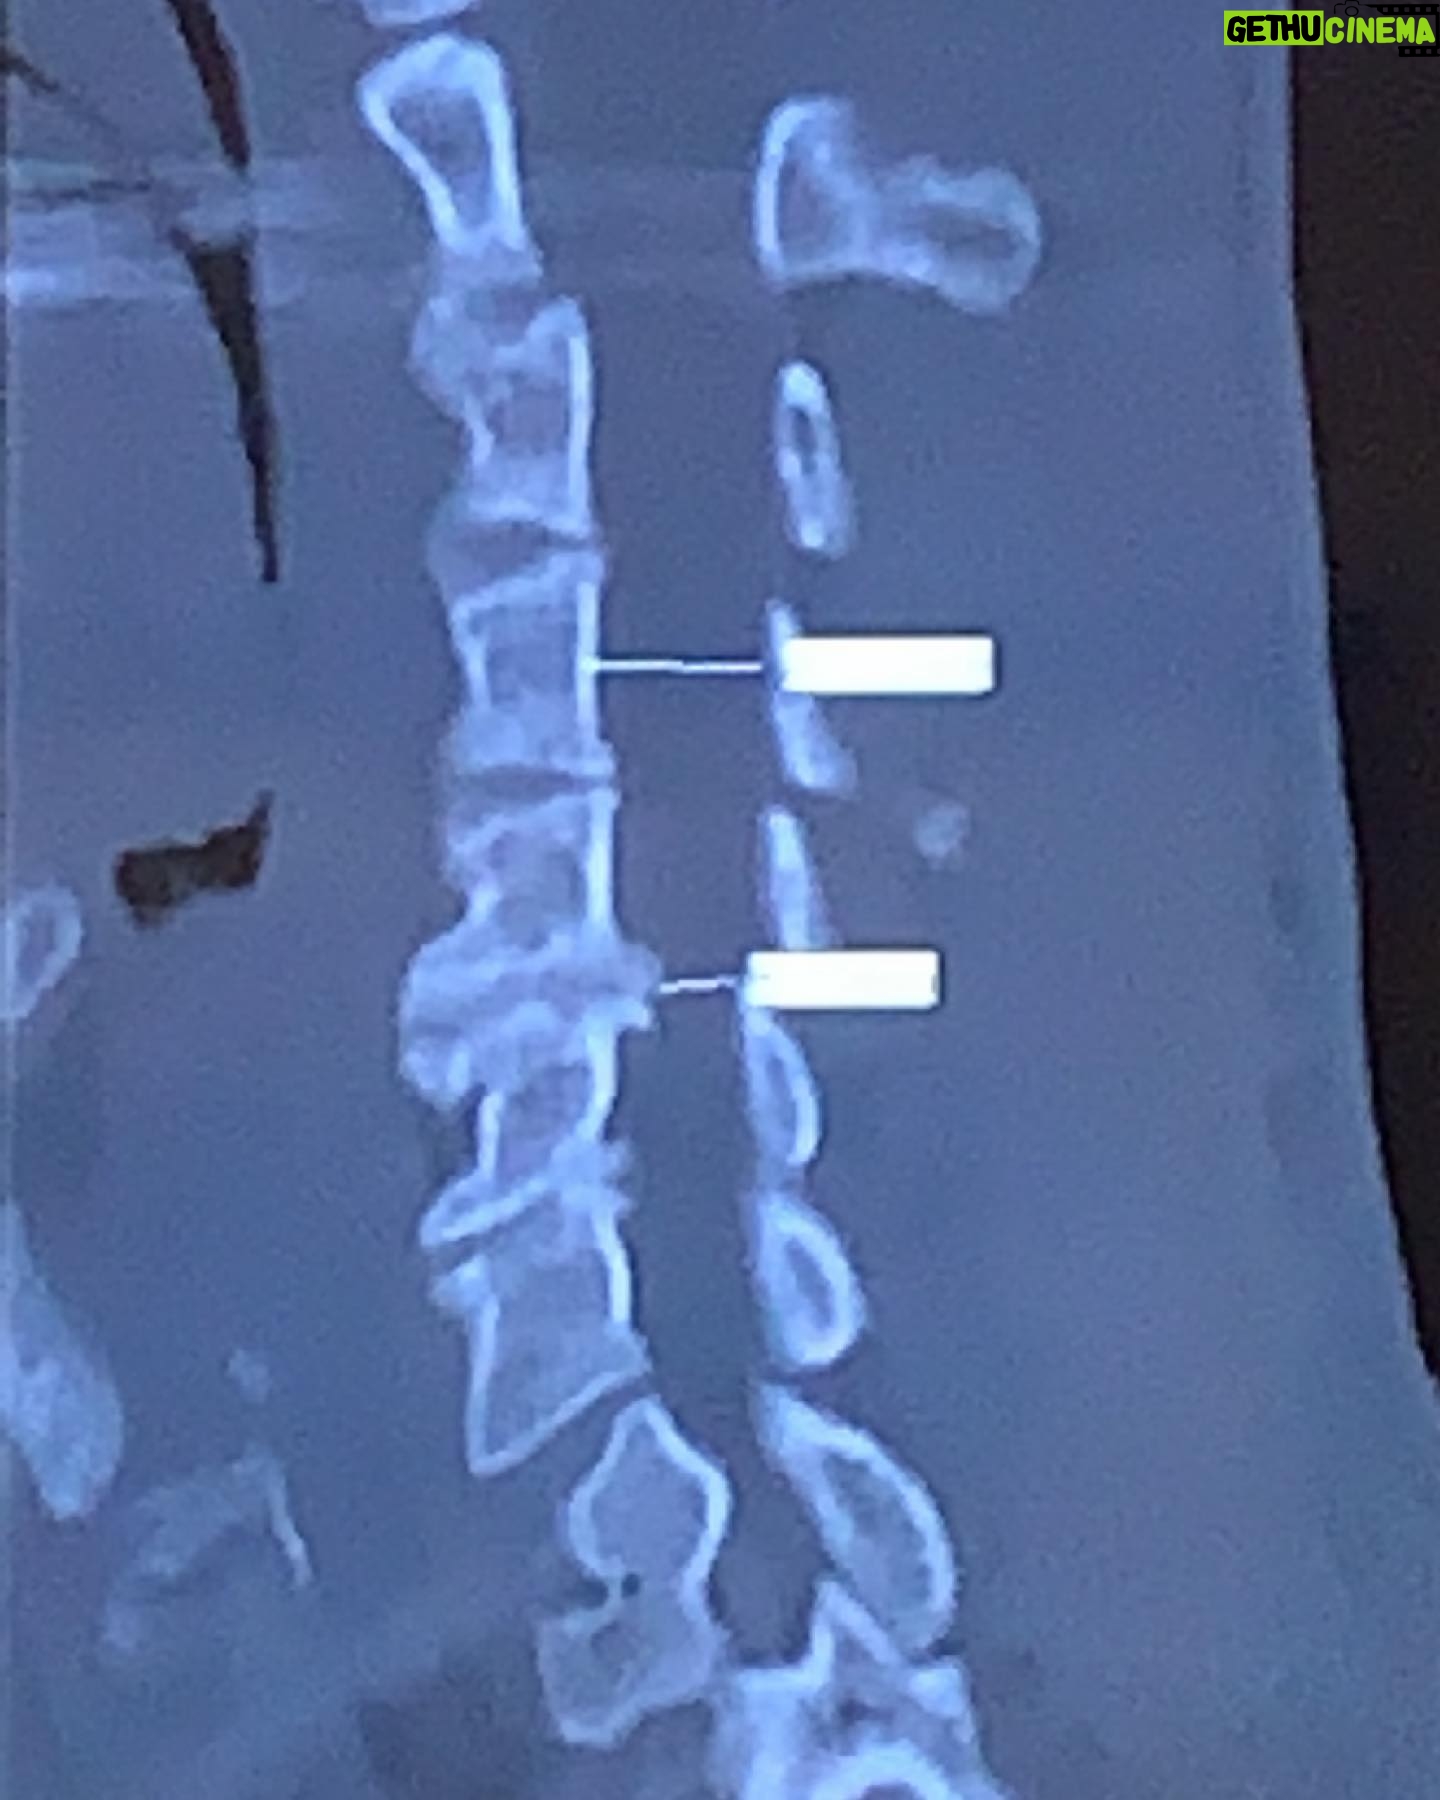

11.1K Likes – Danny Way Instagram

Caption : Was it all worth it? common question I’m frequently asked, my answer is ABSOLUTELY !!!! Not sure if you can see what’s going on here but this is a CT scan of my neck showing loss of curve, 2 crushed discs C5-7, bone spurring and serious narrowing of the spinal canal. This is one of the many situations I’ve had to deal with most of my adulthood/ career with no tangible solution. I did this hitting the sandbar surfing when I was 18. I’ve accepted the injuries that western medical has no cure and just kept charging with the fuck it why would I turn back now, full speed ahead till the wheels fall off mentality. We are all human regardless of the mindset we develop to manage pain and bodily dysfunctions. The reality is eventually the consequences that come with living a reckless risk taking lifestyle catch up with all of us. I have been pushing myself beyond the physical safe zone since I started to walk and once I discovered vehicles it was really on. Not all of my injuries have been from skateboarding but an accumulation of all the physical passions I’ve pursued with no reservations to ever play it safe, all in always. I don’t ever want to slow down so I’m doing everything can to keep it going. This neck injury is just one on my list that I’ve been praying for medical science to figure out along with other injury dilemmas which include severe cartilage degeneration in both of my knees and one of ankles. My only alternatives prior have been fusing C5-7 and total knee and ankle replacement. @bioxcellerator_ has had major success with disc and cartilage regeneration using their progressive approach to stem cell therapy. It all seems too good to be true but we are limited in the USA to what the FDA will allow/endorse which minimizes our access to the most groundbreaking medical discoveries to date. This isn’t the first time I’ve had to travel abroad for medical treatment and it won’t be the last. I plan to share the results from this joint regeneration exploration and hope I can share with others in need and provide hard data on the most cutting edge treatment solutions that actually work. I’ve decided to just turn my athletic career into one big experiment.Likes : 11133